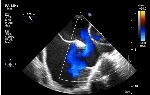

Sinus venosus ASD (also referred to as SVC ASD) is a defect in the failure of the sinoatrial orifice to lateralize completely to the right side during atrial septation.Left venous valve, as well as the septum secundum, fails to fuse with the roof of the atria creating interatrial communication. During this process, the developing pulmonary vein overshoot to the right side making PAPVD a mandatory add-on defect. (Harley ,Thorax 1958 ) It can be referred to as embryonal venous migration defect at the level of RA. In the same sense, it is not a true defect in IAS but a defect in septation between SVC/PV. It may also be referred to as unroofing of RUPV. The so-called Inter atrial communication actually is the confluence point of RUPV/SVC/RA.(See TEE images below)